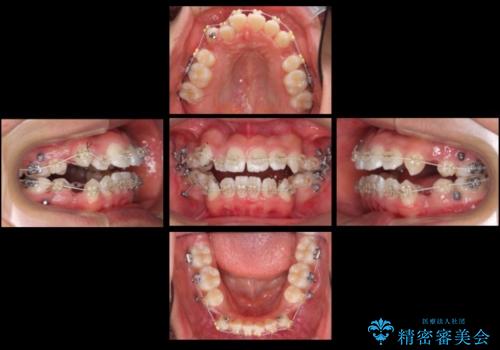

- インビザライン、ワイヤー矯正併用

八重歯や、前歯のオープンバイト(開咬)の症状があり、マウスピース(インビザライン)矯正単独では治すのが難しい症状が複合していました。

八重歯や抜歯したスペースの閉鎖をワイヤー矯正で前半行い、治療後半は目立たないインビザラインでかみ合わせを調整しました。

上の奥歯を後ろ下げるために、矯正用ミニスクリューを使用しています。